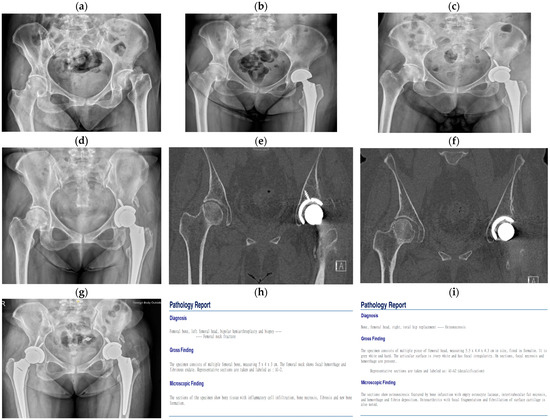

| No. 2 | 52 | Female | Liver cirrhosis | Alcoholic | Subcapital | No | X-ray CT | 1. Bipolar 2. THA |